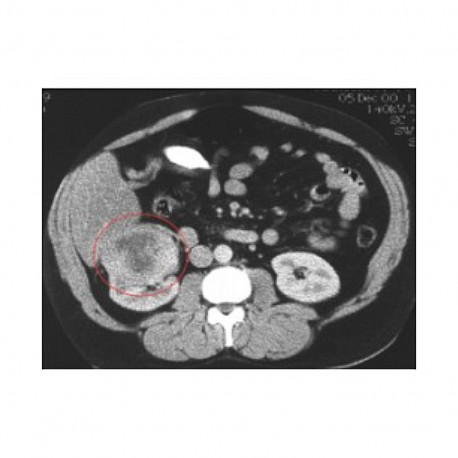

Aujourd’hui, on détecte de mieux en mieux, et de façon toujours plus précoce, les cancers. Dans beaucoup de cas, c’est un progrès. Cependant, les diagnostics précoces révèlent parfois des cancers qu’il n’y a pas lieu de traiter, car les tumeurs évoluent peu. C’est notamment le cas dans le cancer de prostate, que met en évidence le test PSA. De même, dans une moindre mesure, avec le cancer du sein et les campagnes de dépistage systématique. Le risque de surdiagnostic mais surtout de surtraitement est ainsi à prendre en compte lorsqu'on traite de la problématique du dépistage.